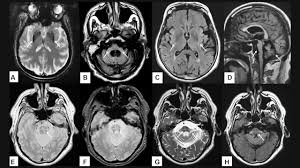

- Chụp cộng hưởng từ (MRI): Có thể cho thấy bất thường ở vùng não.

Chụp MRI có thể cho thấy bất thường ở vùng não khi bị teo đa hệ thống